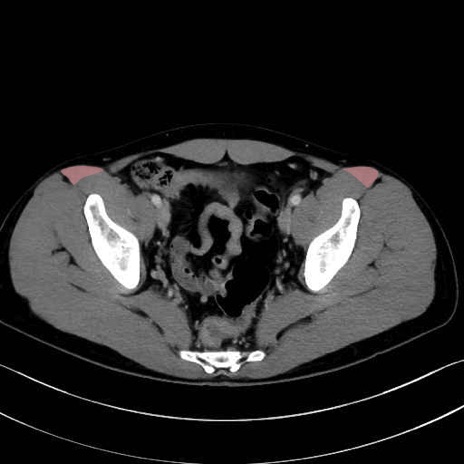

縫工筋(sartorius muscle) のCT画像の解剖

4. 深層外旋六筋(股関節の深部)

梨状筋 (Piriformis)

内閉鎖筋 (Obturator internus)

外閉鎖筋 (Obturator externus)

大腿方形筋 (Quadratus femoris)

3. 殿部の筋肉(表層・中層・深層)

大殿筋 (Gluteus maximus)